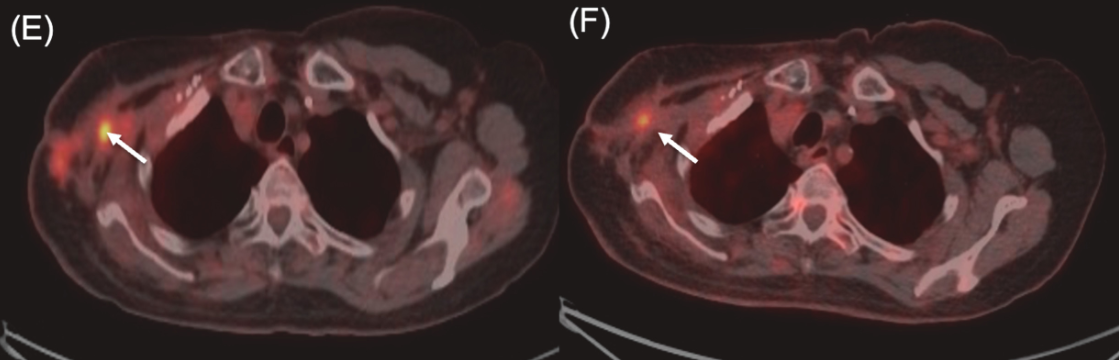

近期,一项发表于《Critical Reviews in Oncology/Hematology》的Meta分析,系统评估了硼中子俘获疗法(BNCT)治疗局部复发性头颈癌(LRHNC)的疗效与安全性。